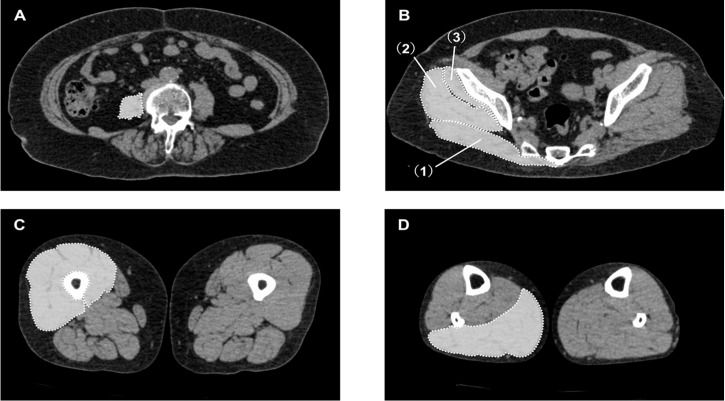

Methods: This was a single-institution retrospective cohort study. Participants in this study were patients undergoing primary THA. Fatty infiltration in each muscle (bilateral psoas major, gluteus maximus, gluteus medius, gluteus minimus, quadriceps, and triceps surae) was assessed using non-contrast X-ray computed tomography images obtained during a detailed preoperative examination. The outcome of this study was the normal comfortable walking speed at 2 weeks after THA. Decreased walking speed was defined as less than 0.8 m/s (non-decreased group, coded 0; decreased group, coded 1). Multivariate logistic regression analysis was used to analyze the relationship between fatty infiltration of each skeletal muscle and walking speed.

Results: A total of 168 participants were included in the analysis. On the operative side, the analysis identified fatty infiltration of the gluteus medius (odds ratio, 0.95; 95% confidence interval, 0.91-0.99) as a determinant of decreased walking speed after THA. On the nonoperative side, the analysis identified fatty infiltration of the quadriceps (odds ratio, 0.91; 95% confidence interval, 0.83-0.99) as a determinant of decreased walking speed after THA.

Conclusions: In patients undergoing THA, increased fatty infiltration of the gluteus medius on the operative side and the quadriceps on the nonoperative side were associated with decreased walking speed at 2 weeks postoperatively.